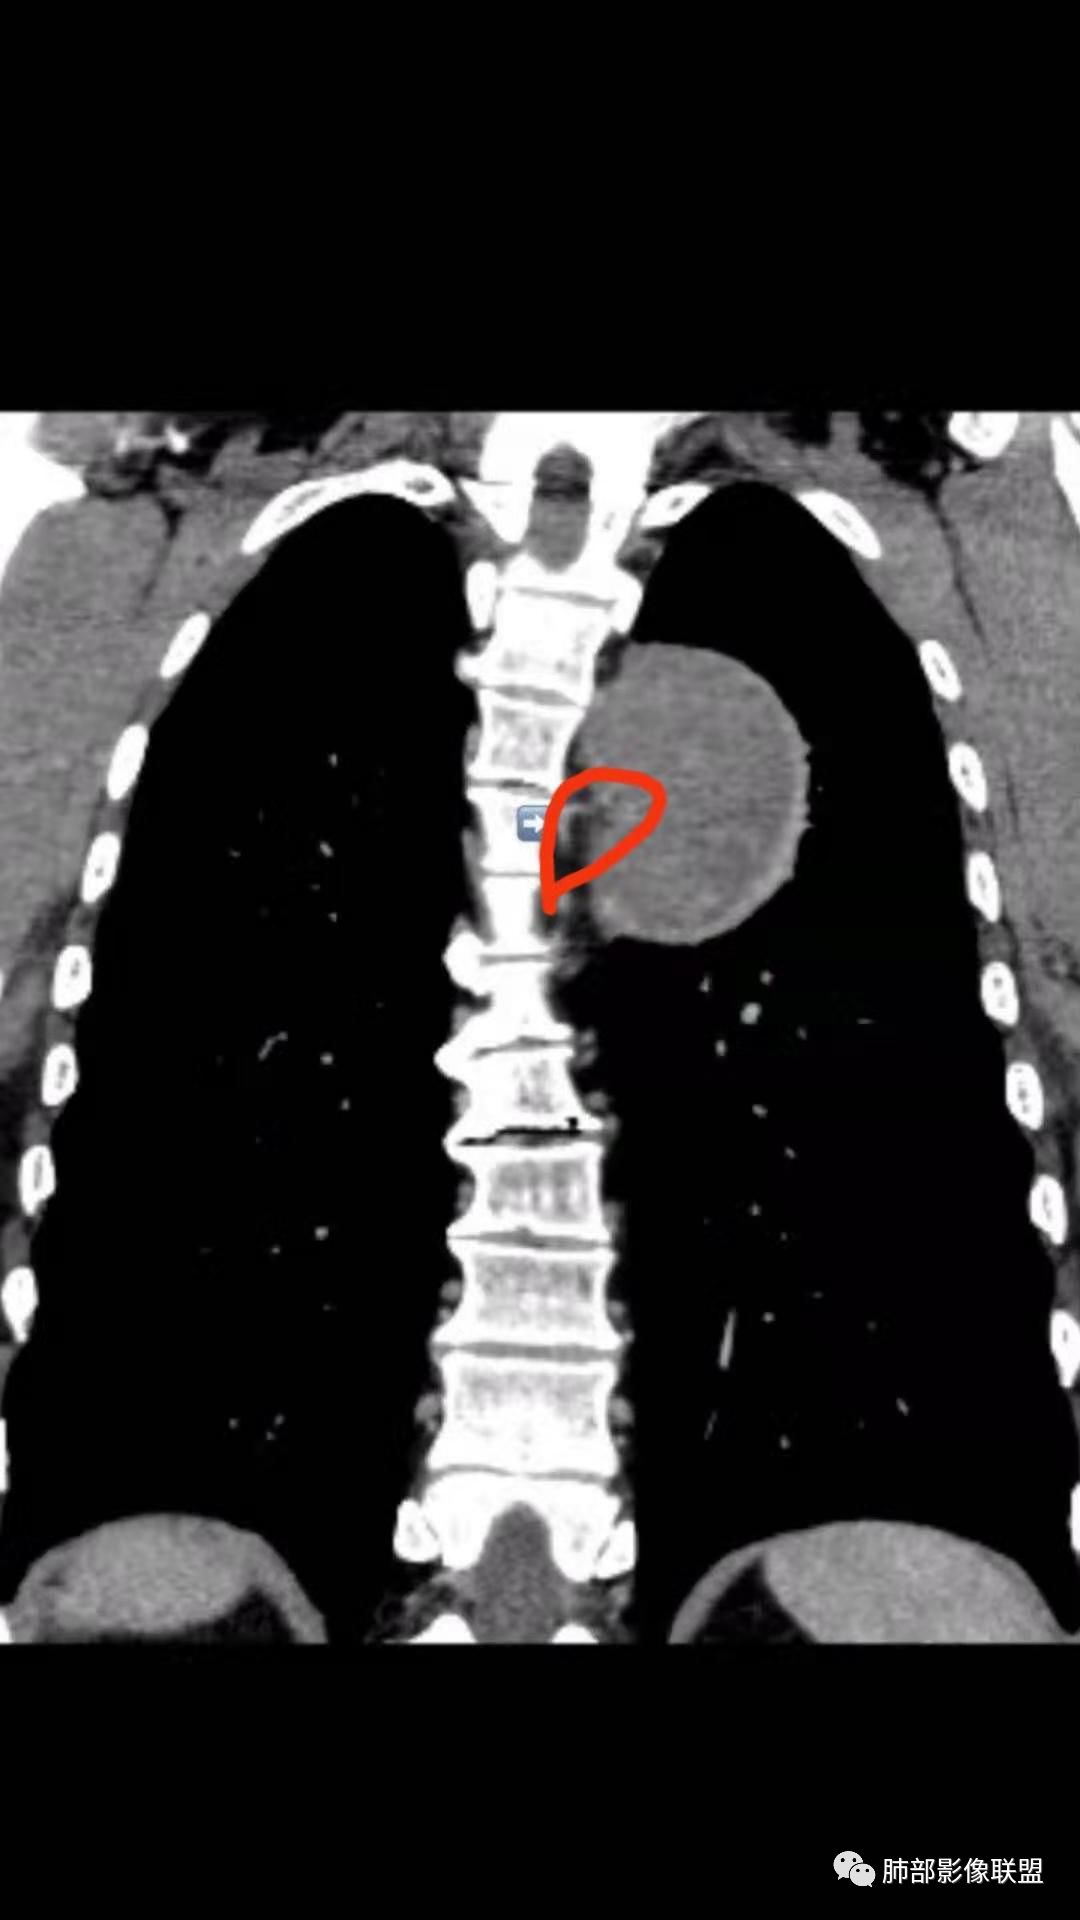

红日东升:左侧胸椎旁肿块,边缘清晰光整,冠状位见D字征,未见支气管进入,肺组织受压表现,定位肺外。轻度强化,密度稍不均匀,临近肋骨变细,未见肺动脉供血,考虑良性肿瘤,神经源性可能。右肺下叶病灶,轻度强化,血管显影,边缘平直、凹陷,考虑炎性病变。

张立:左侧胸椎旁肿块,边缘清晰光整,冠状位见D字征,未见支气管进入,肺组织受压表现,定位肺外。轻度强化,密度稍不均匀,,未见肺动脉供血,神经源性肿瘤,节细胞神经瘤可能。右肺下叶病灶,轻度强化,血管显影,边缘平直、凹陷,TB可能。

崇军:左侧胸椎旁肿块,边缘清晰光整,有胸膜尾征,冠状位为D字征,定位肺外。轻度强化,密度稍不均匀,似乎看到肋间动脉供血,未见肺动脉供血,考虑良性肿瘤,神经源性可能。右肺下叶病灶,轻度强化,血管显影,边缘平直、凹陷,层面太少,暂时考虑炎性病变。

长沟流月去无声:中年男性,慢咳起病,左后纵隔可见一大占位,D字征,胸膜掀起,有胸膜尾征,附近肺组织受挤压,血管纹理纠集,瘤肺界面清晰,较均匀轻-中度强化,瘤肺表面可见线样不张之强化影,供血血管来源不易确定,冠状位似乎见一纵隔血管出入,综合考虑神经源性肿瘤:神经纤维瘤,神经鞘瘤?右下外斑片密度影,估计炎性,但本次手术应该未处理。

ZK金:定位:左肺下叶后综合脊柱旁肺外肿块,胸膜尾征,D字征,瘤肺交界面清晰,肺组织受压。影像表现:边界清晰,密度均匀,上下经线略横经。首先考虑神经源性肿瘤,神经节细胞瘤首选,鞘瘤和孤立性纤维瘤鉴别诊断。右肺下叶考虑炎症。

问题是大病灶,而且椎间孔没累及

我们该如何判断其来源于胸膜还是纵隔

M-Imaging :冠状位,还是靠近纵隔来源的

3.降主动脉这一相对固定结构向前方推移,提示病灶相对坚实且有牢固附着点,不支持来自柔软的肺组织。